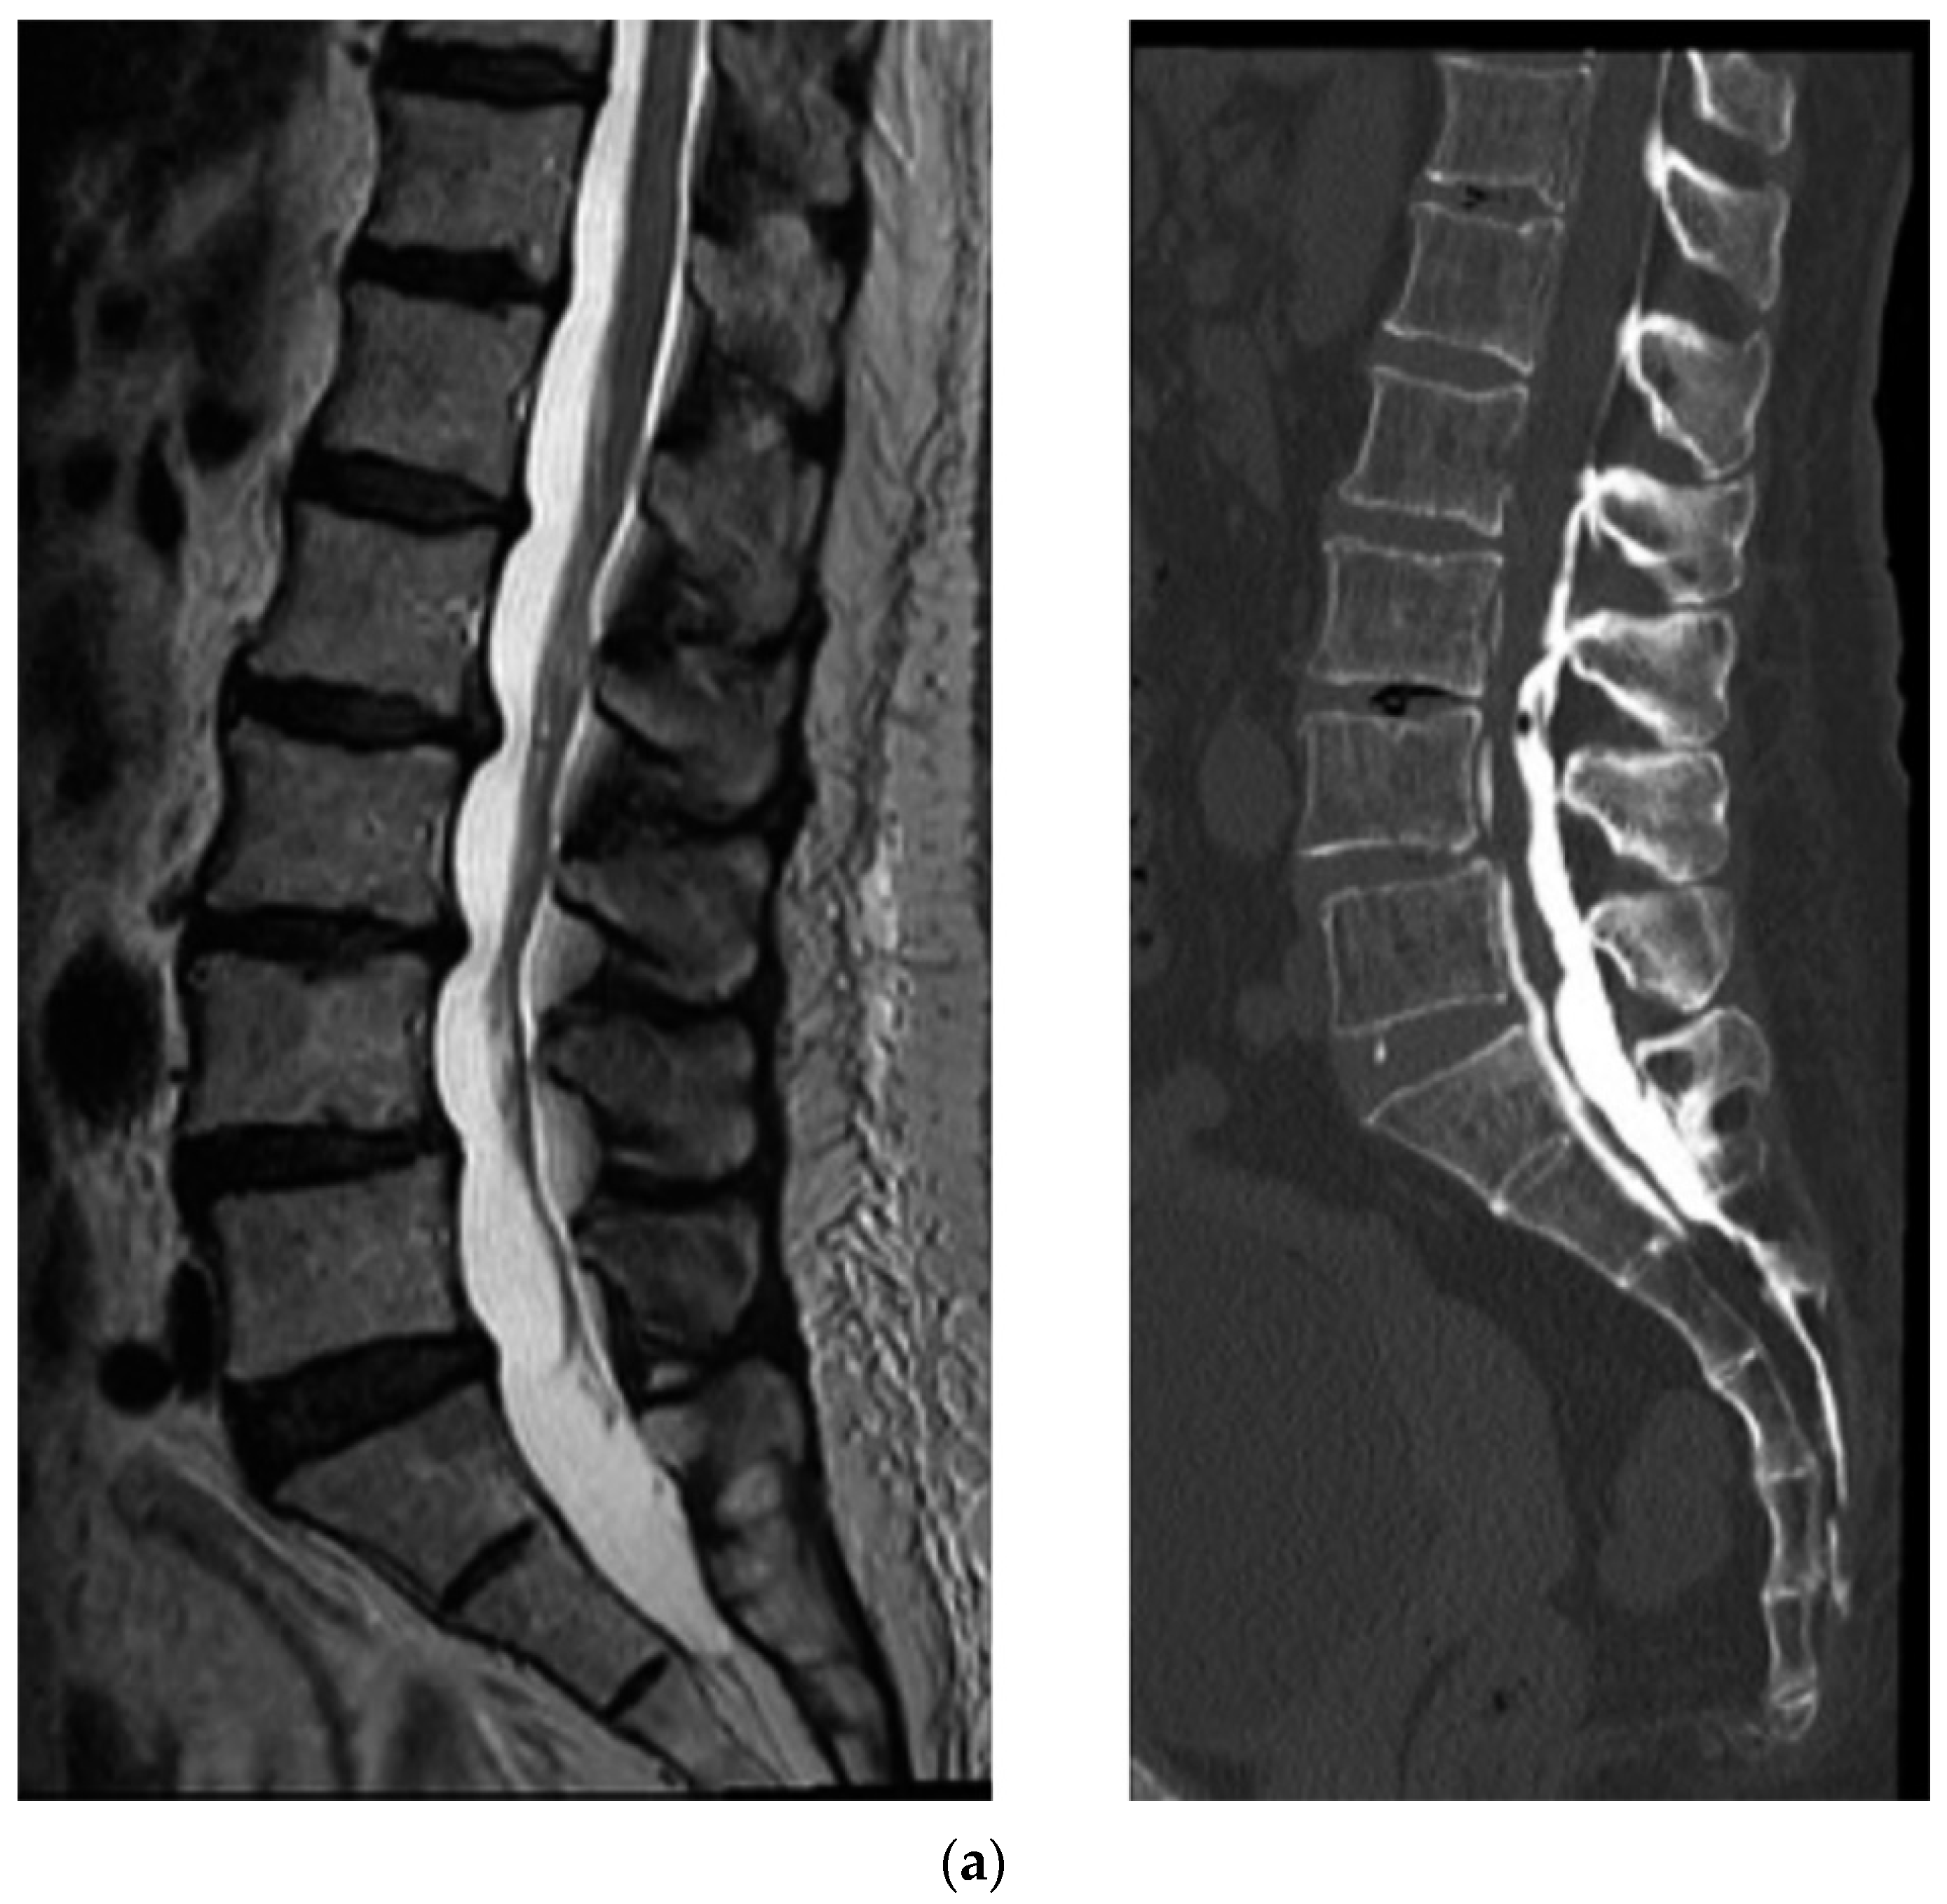

4.1. CT Epidurography